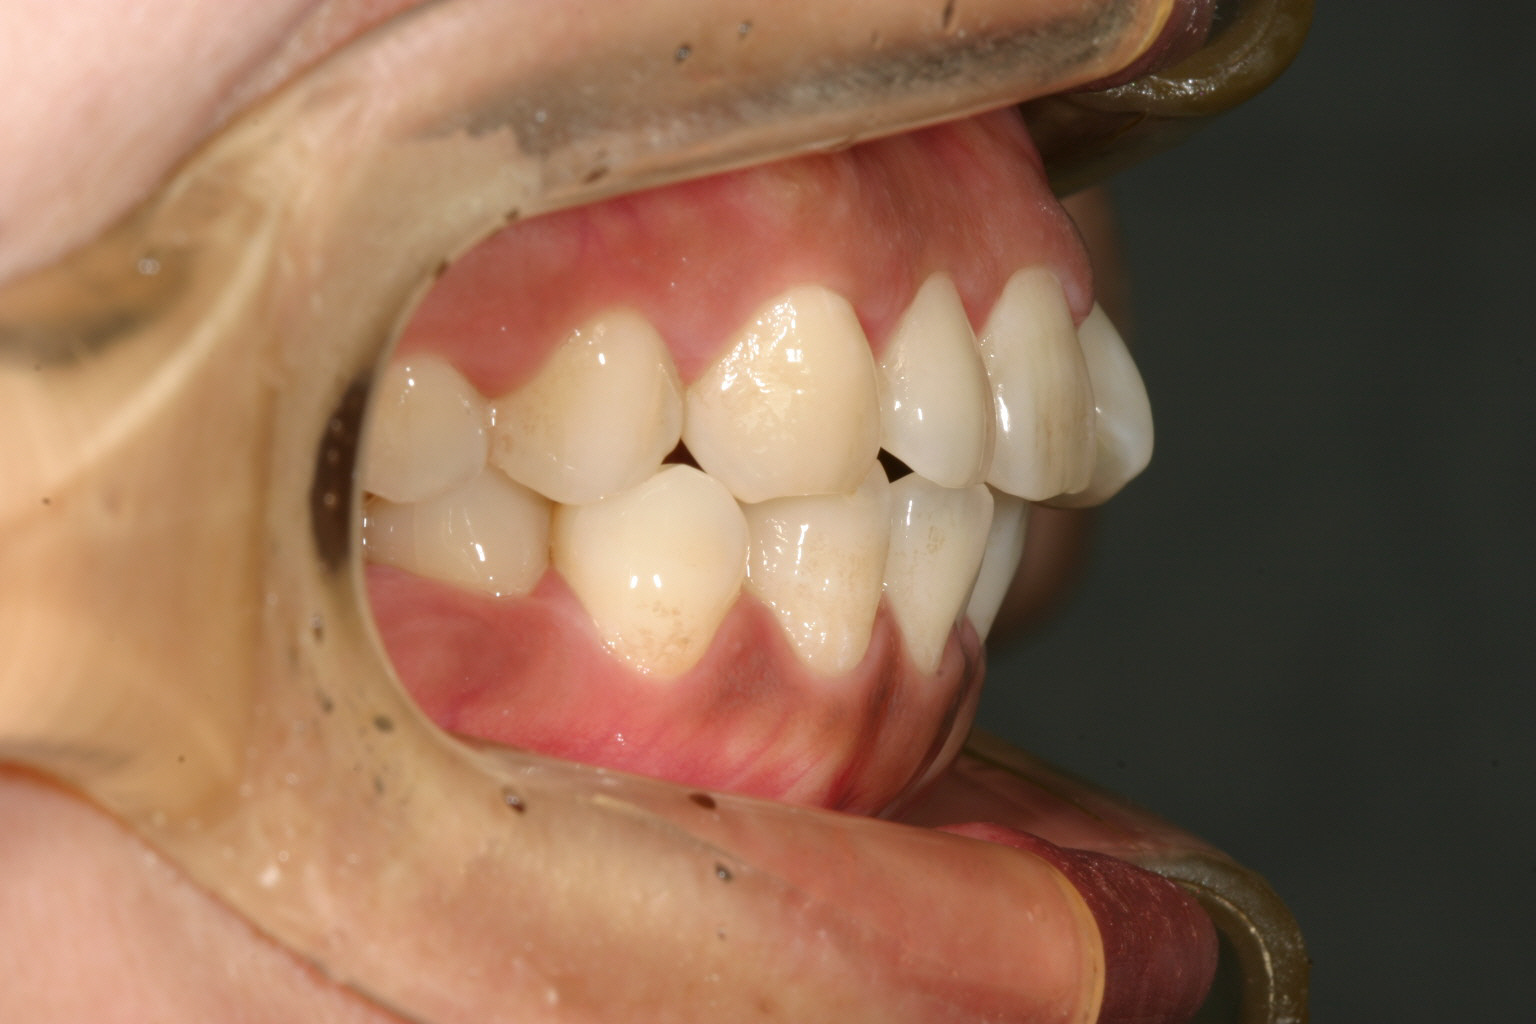

横から見ますと上下ともかなりの出っ歯です。

上の写真と比べてください。 かなり出っ歯が引っ込んだでしょ? 抜歯しなくてもこれだけ引き込める事が出来ます。

今回のケースは非抜歯で上下顎前突をどれだけ引き込める事が出来るかと言う事に挑戦しました。笑

抜歯もせずに何故にこれだけ引き込める事が出来るかと言いますと、インビザラインはデジタル矯正ですから矯正以前にコンピューターで何処にどれだけの隙間を入れればどのように並ぶかと言う事をシュミレーション出来る為、先に理想となる歯並びをシュミレーションしておき、そこで算出された通りに歯と歯の隙間を削れば簡単にこの様な治療が出来るという事になります。

しかし、いくらでも削れる訳じゃなく最大で隙間で0.5mmとしています。